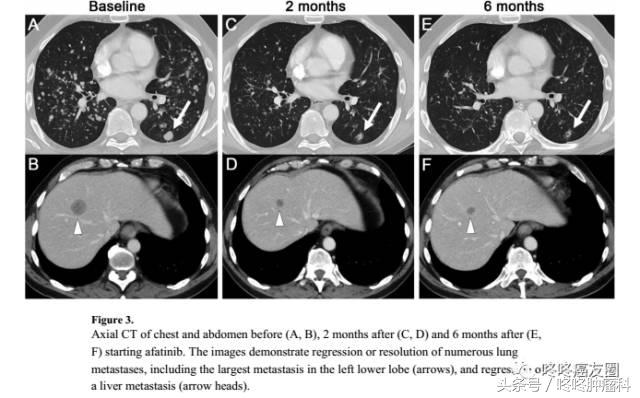

这是一个携带有HER2基因20外显子775位YVMA插入突变的病人,在接受了四五种其他药物的治疗纷纷失败以后,尝试了阿法替尼,用药2个月后,病灶就明显缩小了。